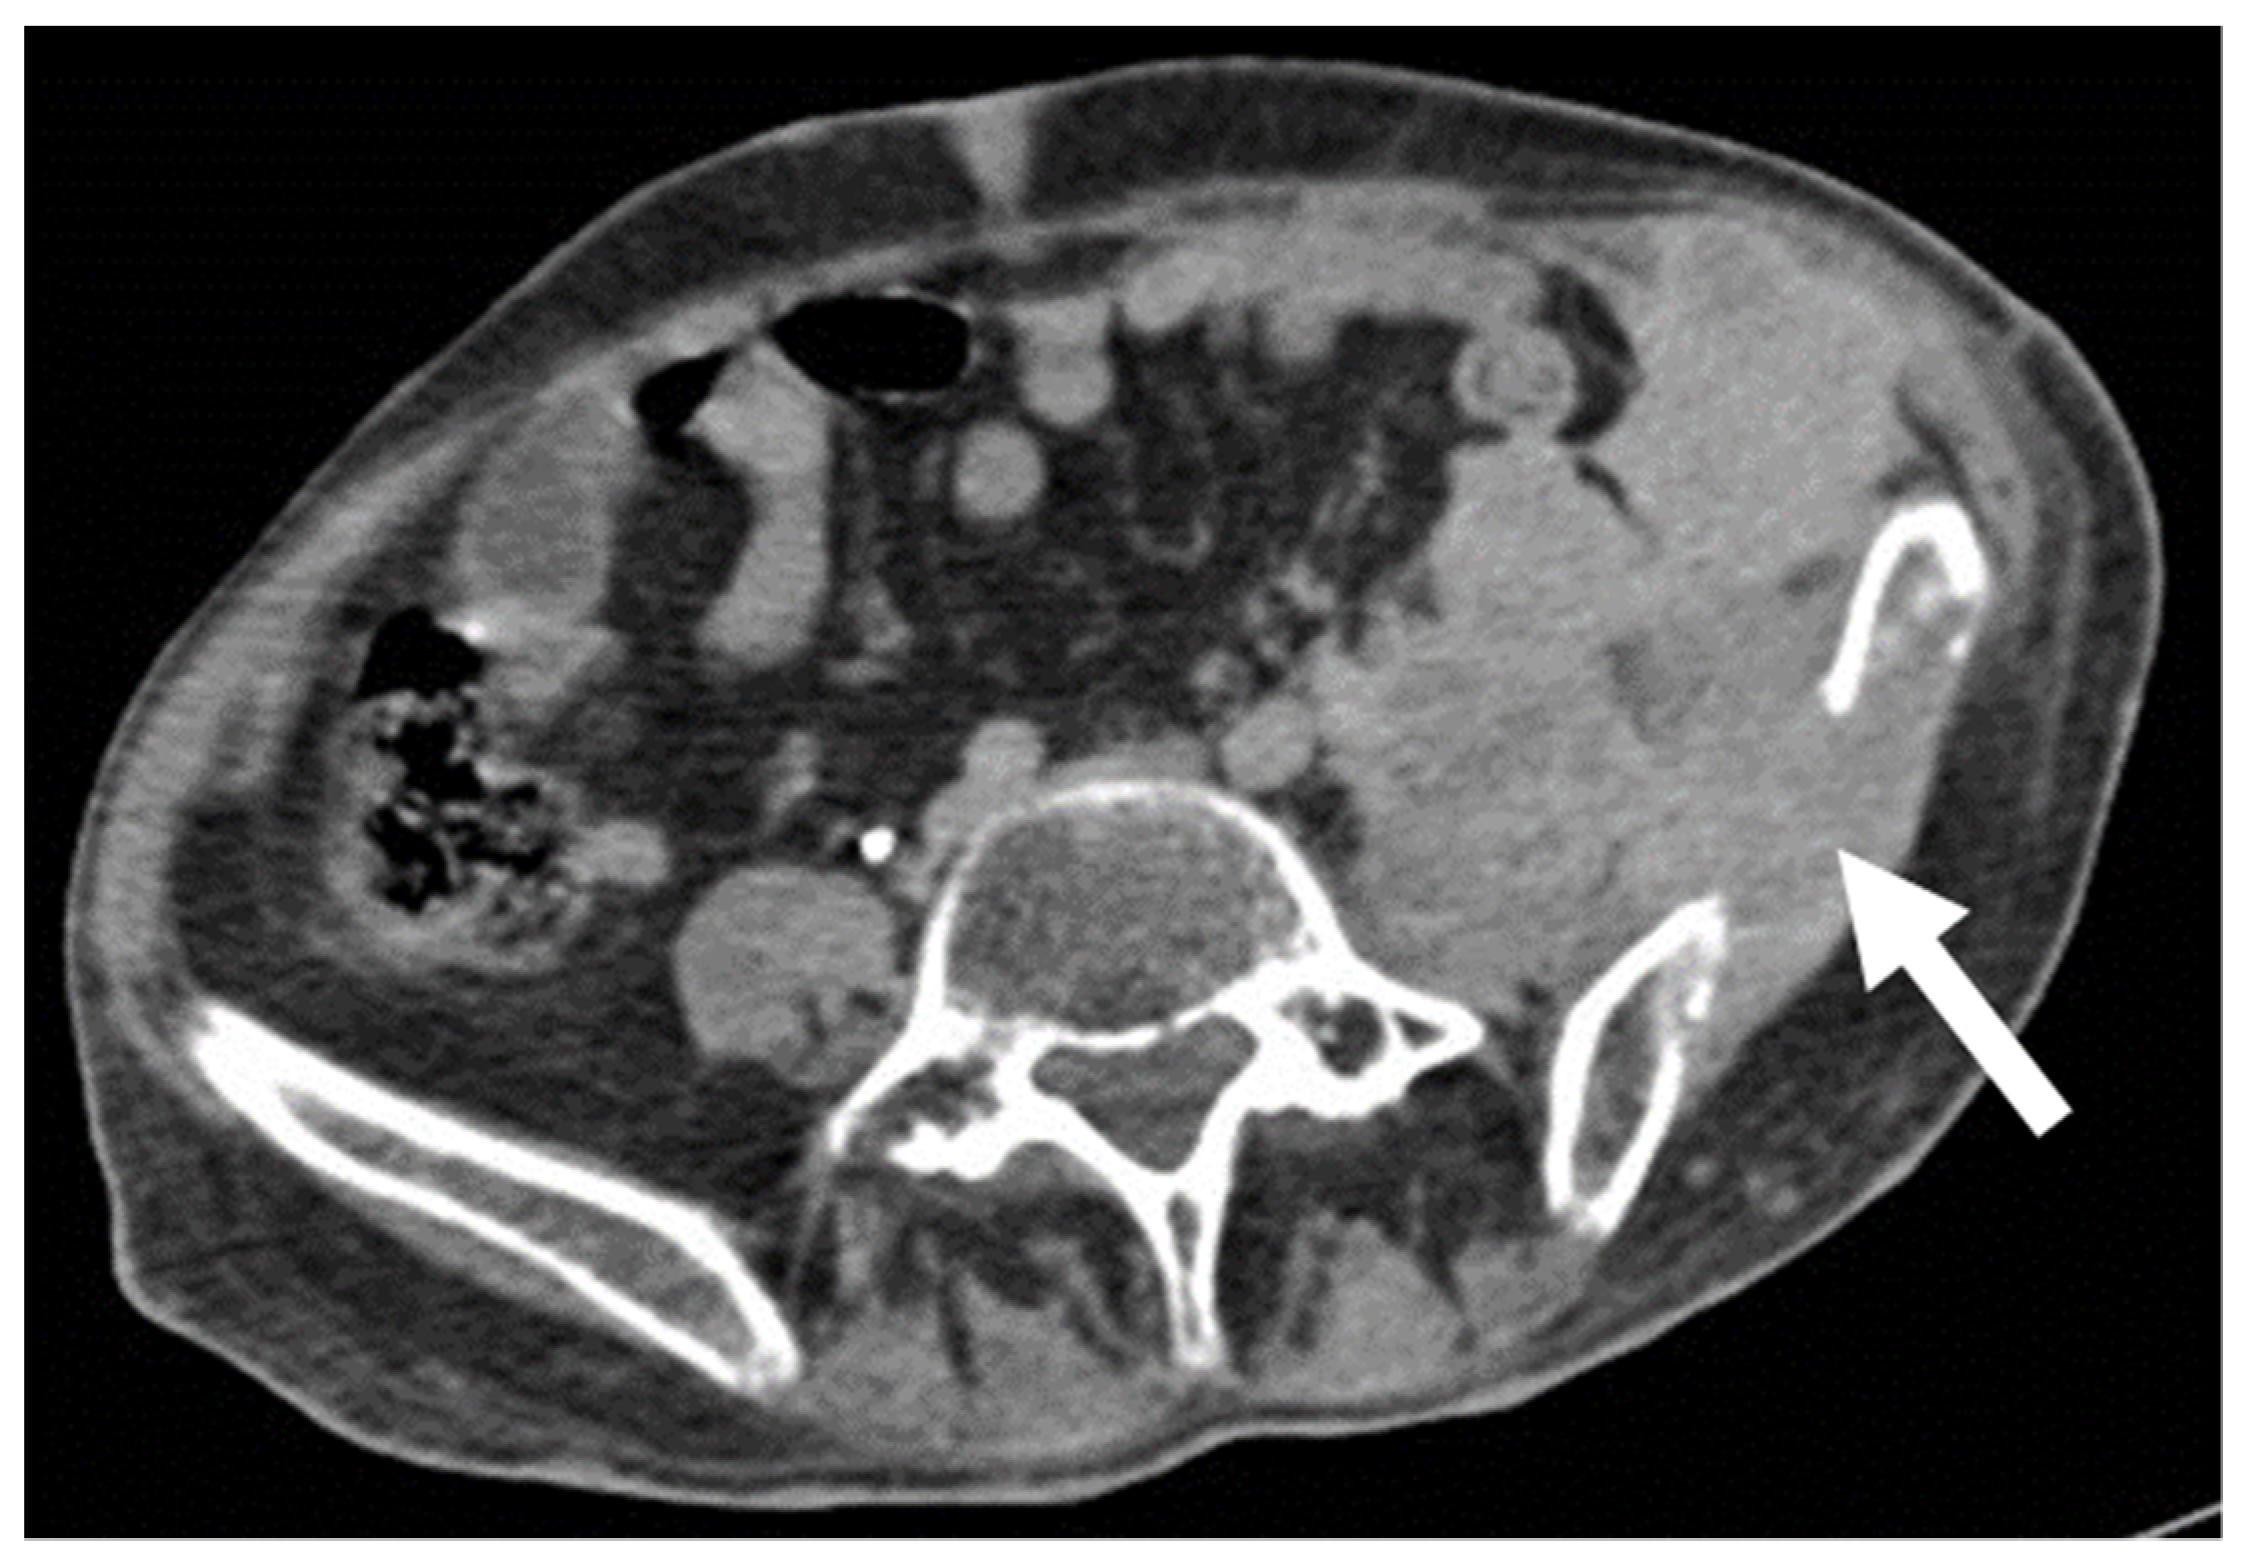

- Desmoplastic Small Round Cell Tumor (DSRCT): rare, highly aggressive sarcoma of adolescents, which primarily involves the serosal surfaces of the abdominal cavity infiltrating the abdominal wall [30,31,32]. Classic findings include bulky multiple, hypoattenuating, soft-tissue masses, with omental, serosal, and rectovesical involvement [31,32] and typical punctate or amorphous calcifications [32]. Modest heterogeneous enhancement is seen on arterial phase, without prolonged enhancement or portal washout [31,32] (Figure 10). On MR, DSRCTs are heterogeneously iso- to-hypointense on T1-w images, with hyperintense foci due to intratumoral hemorrhage [32].